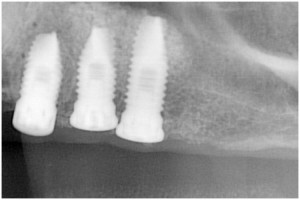

杉山3 埋入時杉山4 左上56サイナスリフト・拡大写真